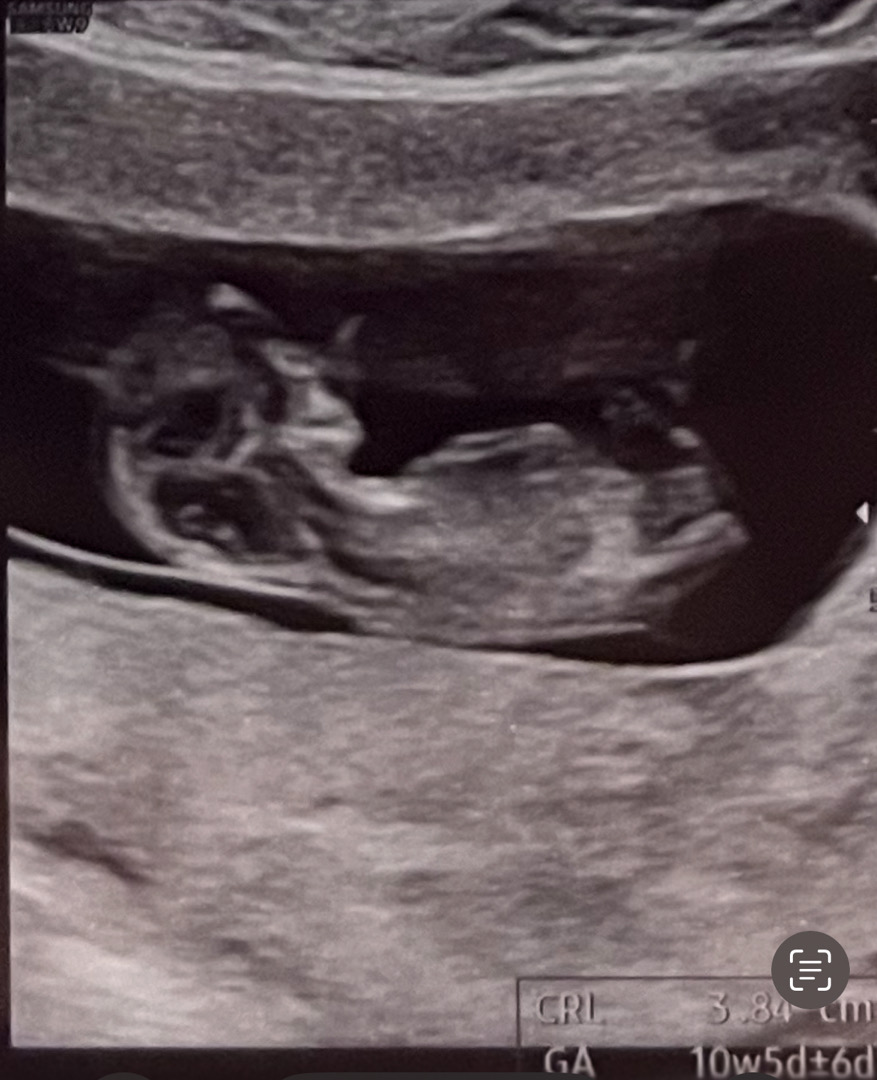

성별 각도법 아시는 분?!

딸일 것 같은데.. 각도법 보실 줄 아시는 분 계실까요?!